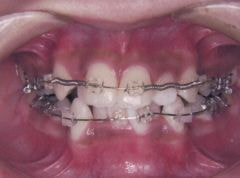

装置装着後